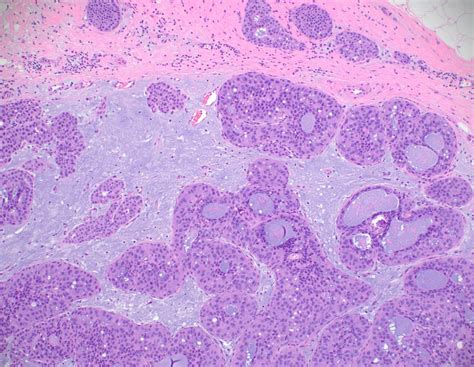

If a needle biopsy reveals Atypical Ductal Hyperplasia, your doctor will likely recommend an excisional biopsy (often called a surgical biopsy). This is a standard procedure because a needle biopsy only takes a tiny sample of the tissue. Sometimes, the initial biopsy may have missed a larger area of cancer or higher-grade atypical cells located elsewhere within the same lesion.

During an excisional biopsy, the surgeon removes the entire area of concern along with a margin of healthy tissue. This allows the pathologist to examine the entire lesion to confirm the diagnosis and ensure no invasive cancer is hidden nearby.